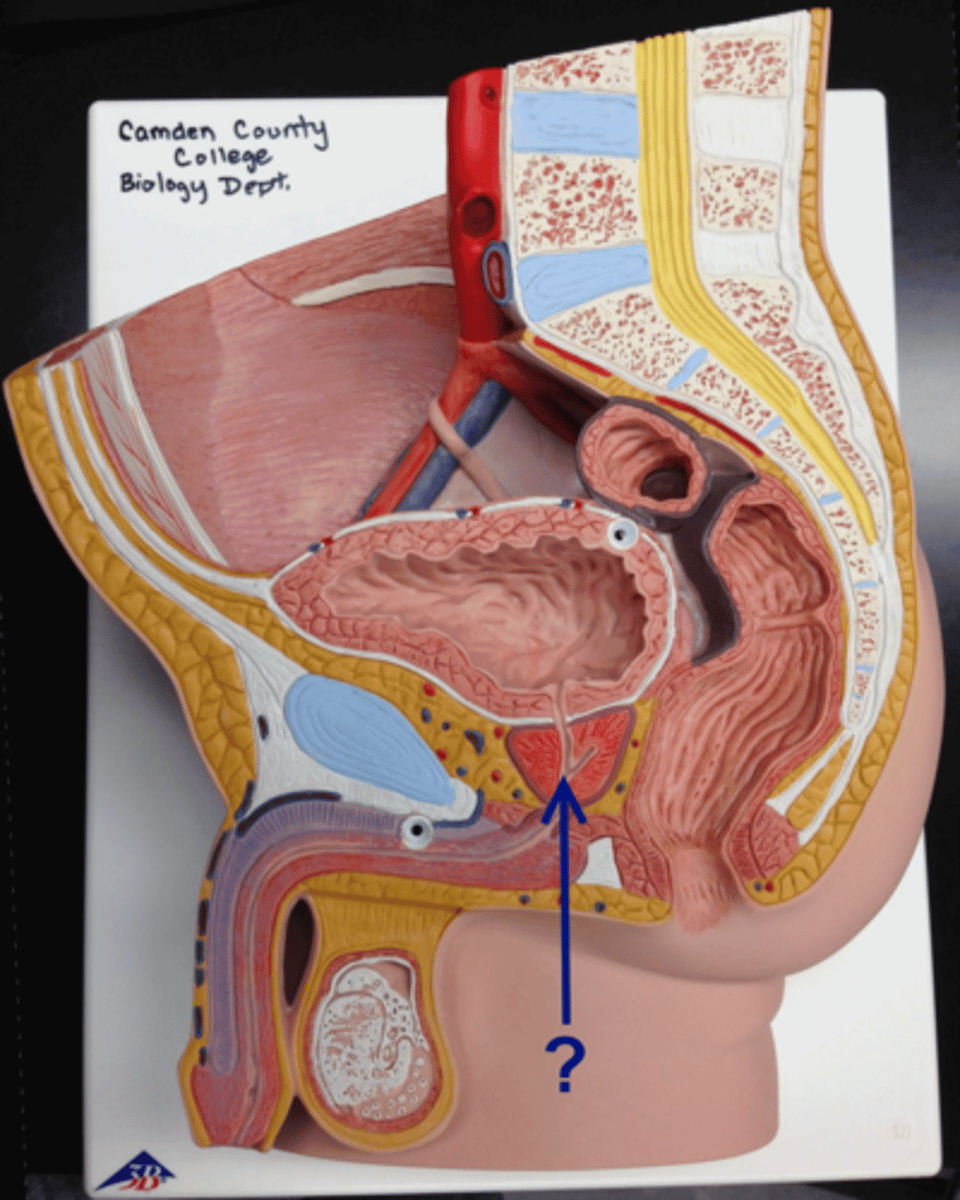

Chapter 30 Anat Phys: Male Reproductive System

Prostate gland

Bulbourethral gland

Urethra

Urethra

Prostatic urethra

Membranous urethra

Spongy urethra